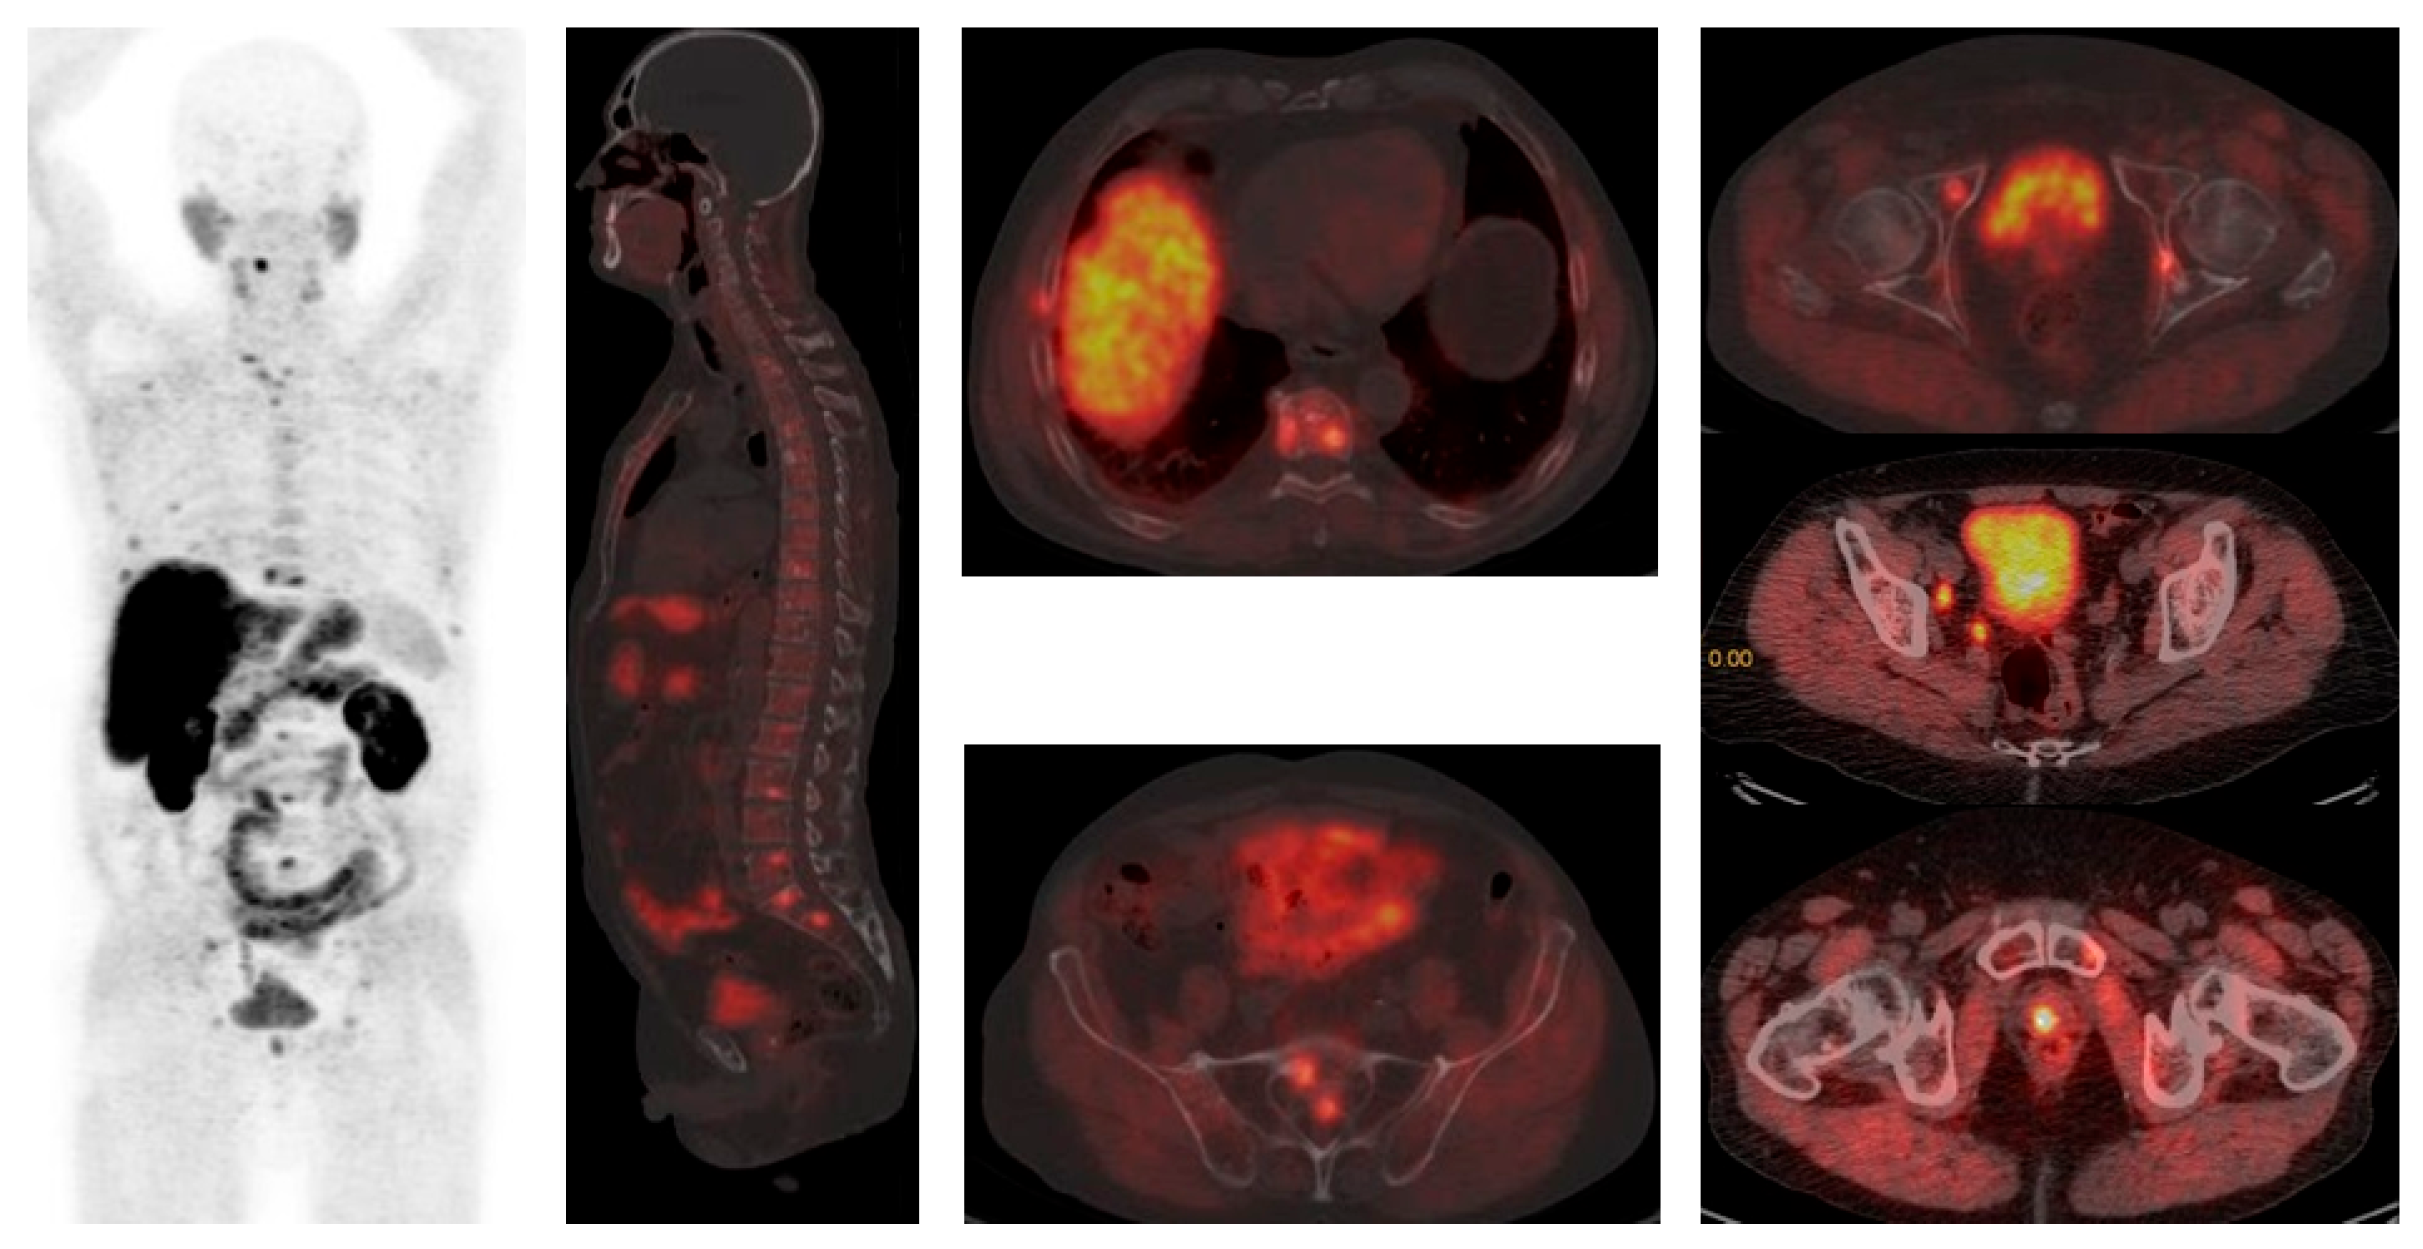

2.4. PSMA-Targeting Radiopharmaceutical PET/CT